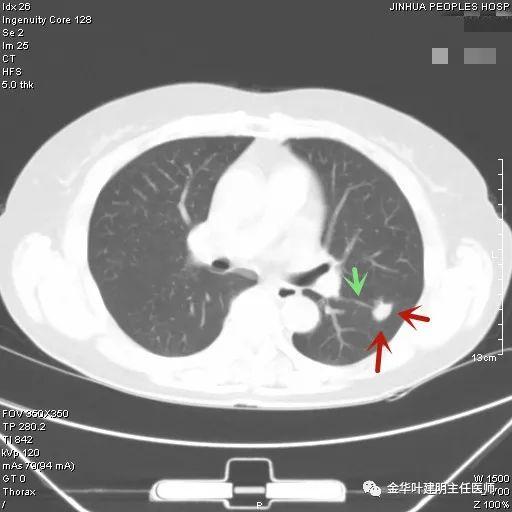

上图示结核。我们发现其有明显的卫星灶,如绿色箭头所示,主病灶处也是周边有模糊区域,病灶整体密度较为均匀(肿瘤容易生长不均致密度欠均匀,显杂乱)。

叶建明谈结节:检查发现肺实性结节怎么办?个人版实用指南